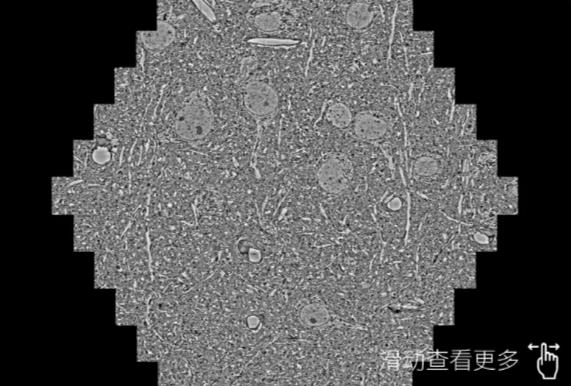

鼠脑切片。左图使用本溪蔡司本溪扫描电镜MultiSEM706对165μmx143pm面积区域成像,耗时仅需1.5秒。右图为鼠脑切片中30μm区域放大效果。样品由芝加哥大学B.Kasthuri提供。

使用蔡司高速本溪扫描电镜MultiSEM对1mm²人脑皮层组织进行高分辨成像,并对其中的各种细胞结构进行三维重构分析。左图展示了2x3mm²组织平面中锥体神经元的三维重构效果。右图显示了局部体积神经元三维重构。图像由哈佛大学chtman实验室提供,渲染图由D. Berger 制作。